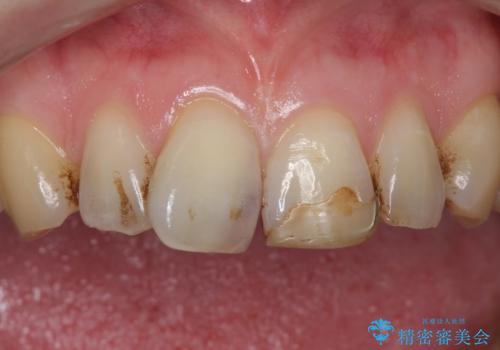

- 前歯のプラスチックの詰め物が気になると来院された患者様です。

左上の前歯に詰められたプラスチック(コンポジットレジン)は、劣化し変色していました。

レジンを除去したところ二次う蝕を認めたため、丁寧に虫歯をとりました。